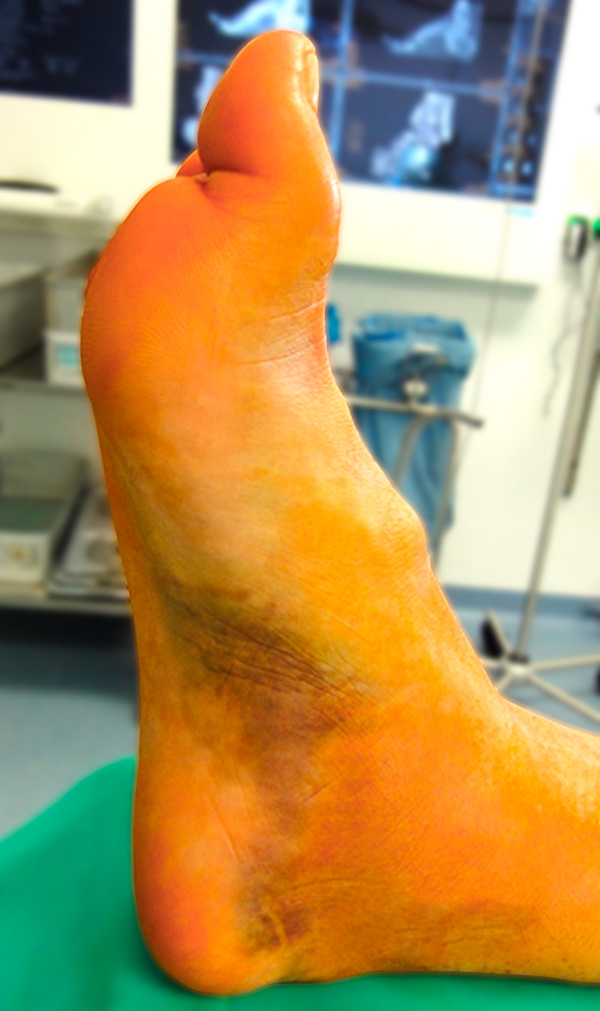

Aufgrund des vulnerablen Weichteilmantels im Bereich des Sprunggelenks weisen dislozierte zentrale Talusfrakturen (Korpus, Hals) häufig Störungen der Hauttrophik auf. Dislokationen sind meist augenfällig (Abb. 2) und die dislozierten Fragmente lassen sich perkutan tasten. Zudem ist meist eine abnorme Fußfehlstellung bei Luxationsmechanismen erkennbar. Hier ist insbesondere bei Fragmentdruck auf die periphere Durchblutung zu achten. Eine initiale Dopplersonografie oder die Indikation zur Kompartmentdruckmessung sollte durchgeführt werden.